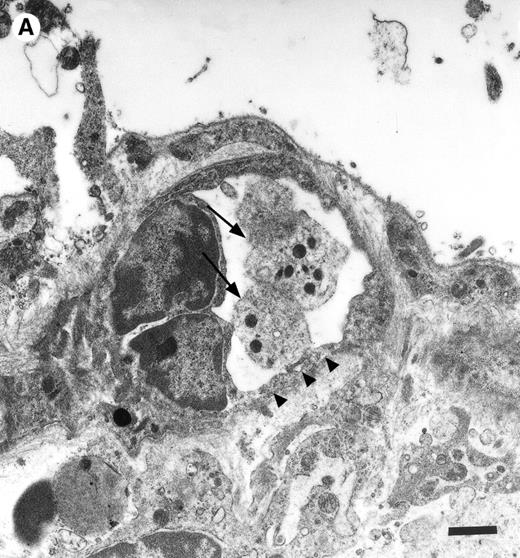

In the physiologic state without I/R, circulating platelets rarely interacted with the microvascular endothelium (Figs1 and 2). Few platelets were observed rolling along the endothelial cell lining of arterioles and postcapillary venules (0 ± 0 and 3 ± 1 platelets/s/mm, respectively). At the same time, only 26 ± 14 and 28 ± 11 platelets were found firmly attached per mm2endothelial cell surface of arterioles and venules, respectively. In contrast, 1.5 hours of ischemia dramatically enhanced platelet-endothelial cell interactions immediately after postischemic reperfusion (Figs 1 and 2). As reported earlier, postischemic platelet accumulation involved arterioles, as well as venules. More than 15 platelets/s/mm vessel diameter were seen rolling along the arteriolar and venular vessel wall, respectively. At the same time, the number of firmly adherent platelets had increased 20- and 12-fold in arterioles and venules, compared with sham-operated animals (Fig 1). Platelet aggregation was a prominent phenomenon. Electron microscopy demonstrated that single or aggregated platelets adhered directly to endothelial cells; obvious defects in the endothelial cell layer were not detected (Fig 3).

Platelets in postischemic microvasculature visualized by electron microscopy. There are no defects in the endothelial cell layer (arrowheads) Platelets (arrows) attach directly to endothelial cells (arrowheads). Bars represent 1 μm. Original magnifications: 7,000× (A) and 12,000× (B). NCL, endothelial cell nucleus.

Endothelial denudation was not observed in the present study, as demonstrated by electron microscopy. Instead, the deposition of fibrinogen occurred directly on the endothelial cell surface, indicating that the attachment of fibrinogen to endothelial cells might be mediated by a fibrinogen receptor present on the endothelium. Recently, the functional role of ICAM-1 as a novel fibrinogen receptor has been emphasized. ICAM-1 has been shown to contain a fibrinogen recognition site that is distinct from previously recognized ICAM-1 ligand binding regions.34 Through its ICAM-1 recognition, fibrinogen enhances the adhesion of leukocytes to endothelial cells in vitro and in vivo,18,19 and supports transendothelial monocyte migration.35 In addition, fibrinogen–ICAM-1 bridging has recently been demonstrated to mediate platelet adhesion to HUVECs in vitro.21 In the present study, the lack of endothelial ICAM-1 expression attenuated fibrinogen deposition to the postischemic vessel wall. In addition, in the absence of ICAM-1 platelet adhesion was significantly reduced, indicating that through its fibrinogen recognition, ICAM-1 promotes platelet adhesion to the postischemic endothelium in vivo. This mechanism might be of particular importance in mediating platelet adhesion to atherosclerotic lesions, which are characterized by the large deposition of fibrin(ogen) and the increased expression of ICAM-1.36-38 The established role of both fibrinogen and soluble ICAM-1 as a major risk factor for myocardial infarction further highlights the potential pathophysiologic relevance of platelet adhesion to endothelial cells via fibrinogen bridging to ICAM-1.39-41